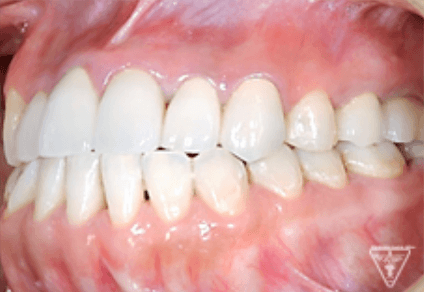

治療前

治療後